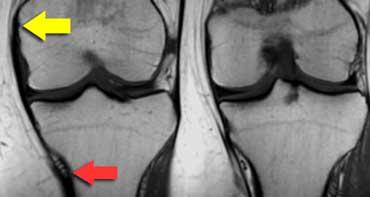

MCL từ lồi cầu trong (mũi tên vàng) đến dưới các mạch máu gối dưới trong (mũi tên đỏ), khoảng 7 cm dưới khe khớp.

Dây chằng bên trong

Dây chằng bên trong nông (MCL) chạy từ lồi cầu trong đến điểm bám không chỉ gần khớp mà còn xuống tận 7 cm dưới khe khớp.

Tại điểm đó có ba mốc giải phẫu: động mạch gối dưới trong và hai tĩnh mạch đi kèm (hình minh họa).

Phần sâu của MCL, ngay cả khi bình thường, đôi khi cũng không quan sát được.

Nó nằm sát với sụn chêm trong và MCL nông.

Dây chằng bên trong (2)

Ca bệnh bên trái cho thấy bong gân độ I của dây chằng bên trong.